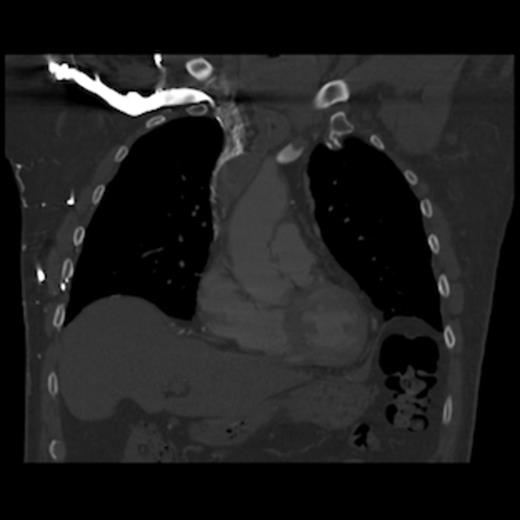

A 67-year old gentleman presented with progressive head and neck swelling and discomfort for several months. His symptoms were pronounced by bending over or straining in the bathroom. His symptoms worsened and he was referred for thoracic surgery consultation after a mass was seen on chest x-ray. He was diagnosed with SVC syndrome secondary to a mediastinal mass, demonstrated best by computed tomography (CT) [Figures 1, 2, 3].

CT of the chest (coronal section) with intravenous contrast: demonstrates large thrombus obstructing the superior vena cava down to the right atrium